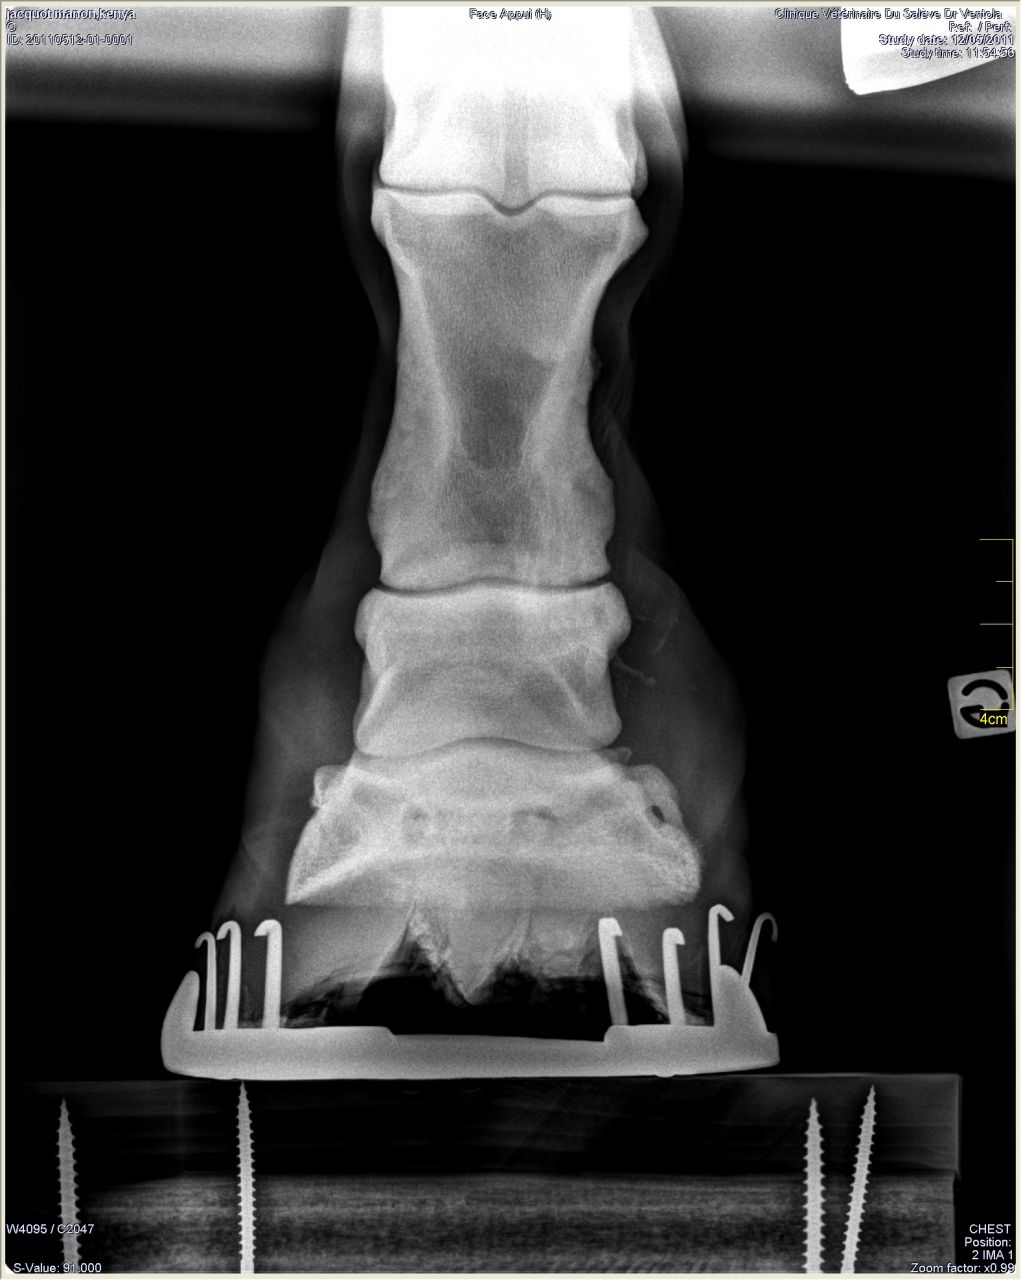

houla,bonjour la radio...d'ailleurs ce n'est meme plus un suros,cela ressemble a un morceau de l'os qui s'est détaché bref,dis moi ce cheval a du avoir un accident non? on peut avoir l'historique? car la effectivement,(et je ne suis pas veto),je pense que toute activite montee est proscrite

voila une radio "normale"

et celle du cheval de ton amie:

on voit bien le morceau qui semble s'etre detache de l'os et avoir migré ....

ce bout d'os parait énorme sur la radio

ben deja on voit bien la deformation des tissus autour

la fracture diséquente à du créer une inflammation et détruire la capsule articulaire. Cette inflammation qui a dû rester trés longtemps crée une zone acide, principe d'équilibration acido-basique-> le calcium et postassium se fixe sur les tissus,calcifie l'artucalion-> arthrose....même à 6 ans

alors, le trcu c'est que la nana qui l'a prit, le cheval lui a été donné ou vendu a un petit prix par une ancienne propriétaire qui n'avait même pas de papier de ce cheval. C'est le vétérinaire qui a determiné son age grace à ses dents. Puis, il a du être débourré mais pas retravailler depuis. Quand la personne (sa propriétaire qui est entrain de le vendre) l'a prit, il avait le sabot (celui de la radio) touis cassé et une enorme croute au dessus. Les gens pensent que c'est lié à un coup. Je n'en sais pas plus.

Pourtant il boite pas, même avec quelqu'un sur son dos. N'a aucune difficulté pour les 3 allures. C'est bizarre que cet os qui se balade ne le gêne pas...